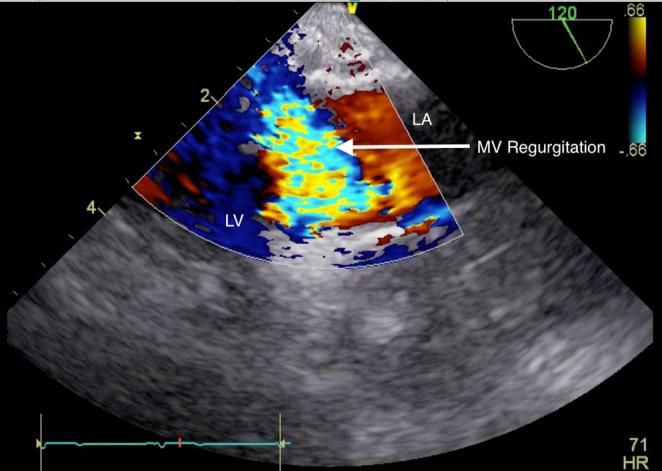

Transoesophageal echocardiography (TOE) has, in certain clinical situations, become an almost universal monitor and diagnostic tool. In the perioperative environment, TOE is frequently used to guide anaesthetic management and assist with surgical decision making for, but not limited to, cardiothoracic, major vascular and transplant operations. The use of TOE is not limited to the theatre environment being frequently used in outpatient clinics, emergency departments and intensive care settings. Two case reports, one of oesophageal perforation and another of TOE utilization in a patient having previously undergone an oesophagectomy, introduce the need for care while using TOE and highlight the need for vigilance. The safe use of TOE, the potential complications and the suggested contra-indications are then considered together with suggestions for improving the safety of TOE in adult and paediatric patients.

在某些临床情况下,经食管超声心动图(TOE)已几乎成为一种通用的监测和诊断工具。在围手术期环境中,TOE经常用于指导麻醉管理,并协助进行手术决策,适用于但不限于心胸、大血管和移植手术。TOE的使用并不局限于手术室环境,在门诊诊所、急诊科和重症监护环境中也经常使用。两篇病例报告,一篇是食管穿孔,另一篇是在一名先前接受过食管切除术的患者中使用TOE,介绍了使用TOE时需要谨慎的情况,并强调了警惕的必要性。随后将一起考虑TOE的安全使用、潜在并发症和建议的禁忌症,以及提高成人和儿童患者TOE安全性的建议。